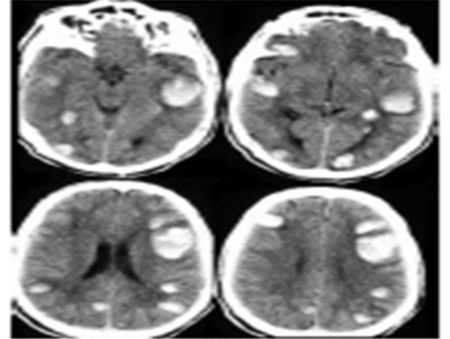

En este caso se trata de una hemorragia en el lugar de la isquemia cerebral en el territorio de la arteria cerebral media izquierda y en el contralateral:

En este caso se cree que además del tratamiento trombolítico, la causa de la hemorragia cerebral puede estar relacionada con una enfermedad subyacente como la angiopatía amiloide (en este caso no se llegó a realizar una RNM cerebral).